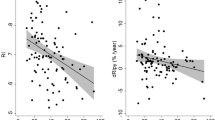

In the ROC curve analysis, when WRF was considered, the RRI at baseline showed an AUC of 0.85 (95% CI, 0.77–0.92) (Fig. 1). The AUC was even greater when the RRI after coronary angiography was considered (0.89; 95% CI, 0.83–0.96). Both the baseline RRI and that after angiography showed an AUC greater than that observed for the baseline GFR-EPI (0.75). The best cutoff value of the RRI (70) was both at baseline and after coronary angiography with a sensitivity that increased (from 79 to 93%) and a specificity that decreased (from 93 to 82%). The proportion of patients with RRI values ≥ 70 increased after coronary angiography in both patients with and without WRF (Fig. 2).

Our results provide new information not only about the baseline pathophysiological background predisposing to WRF but also about the effects of the administration of contrast media on renal circulation. Note that in both patients with and without WRF, the RRI increased after the administration of contrast media, thus suggesting that after coronary angiography, all patients experienced renal vasoconstriction. However, the mean values of the RRI after coronary angiography remained significantly lower in patients without WRF than in those with WRF. This is even more evident when the proportion of patients with RRI ≥ 70 is considered. Among patients without WRF, the percentage of those who showed high RRI values was low before and after CA, whereas it increased among patients with WRF.